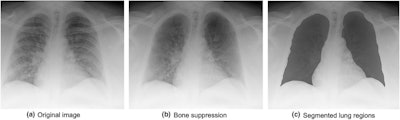

Since it can be difficult to interpret portable chest x-ray images of patients with COVID-19 -- because bone components overlap with the abnormal patterns of the disease -- the group used a bone-suppression technique during preprocessing of the images, testing the model with and without it.

For distinguishing between death and recovery cases, the highest AUCs the model achieved were 0.756 and 0.959, depending on the number of radiomics features included. But its discriminative performance improved when the investigators used the bone-suppression technique, with a sensitivity of 90.9% and a specificity of 95.6% for predicting mortality or survival.